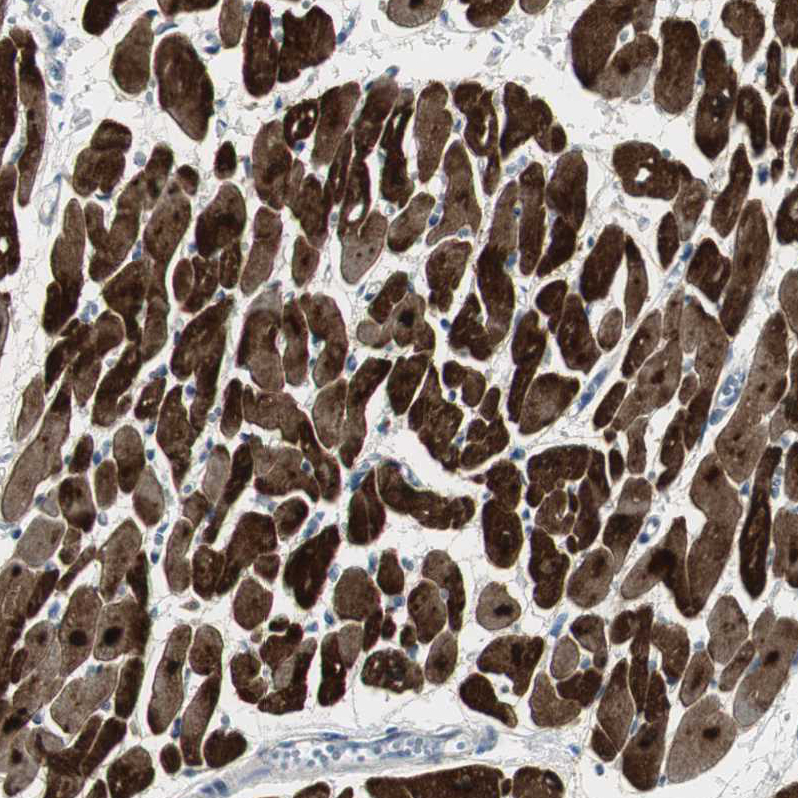

Immunohistochemistry analysis in human heart muscle and liver tissues using HPA006028 antibody. Corresponding FHL2 RNA-seq data are presented for the same tissues.